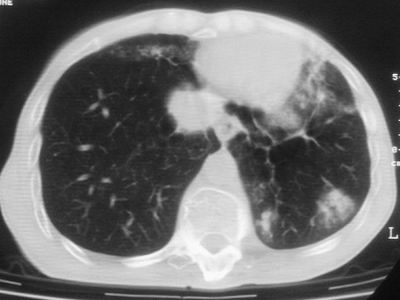

标题: CT11864:男,47岁,反复咳嗽、咯痰、咯血3年,请分析. [打印本页]

患者,男,47岁,反复咳嗽、咯痰、咯血3年,再发5天。痰培养未找到真菌、抗酸杆菌、癌细胞。

左肺上叶体积明显缩小,其内见多发透光区,纵隔向左侧移位,左肺下叶多发班片状病灶,边界模糊,1左肺上叶先天肺发育不全,2左肺下叶肺炎,

左肺上叶结核伴肺纤维化,纵隔移位,左肺下叶感染性病变,建议抗炎抗结核后复查,双肺气肿.

以下是引用xulianj在2008-2-25 21:01:00的发言:[br]左肺上叶结核伴肺纤维化有霉菌球形成,纵隔移位,左肺下叶感染性病变,建议抗炎抗结核后复查,双肺气肿.

考虑:左肺慢纤伴霉菌球形成、双肺全小叶型肺气肿。

1)考虑为:左肺上叶肺结核(空洞形成),伴左下肺感染;不排除霉菌感染可能。2)肺气肿。

左肺上叶结核伴肺纤维化空洞形成并左肺下叶感染,纵隔牵拉移位,建议作进一步检查排除左侧肺霉菌感染可能。